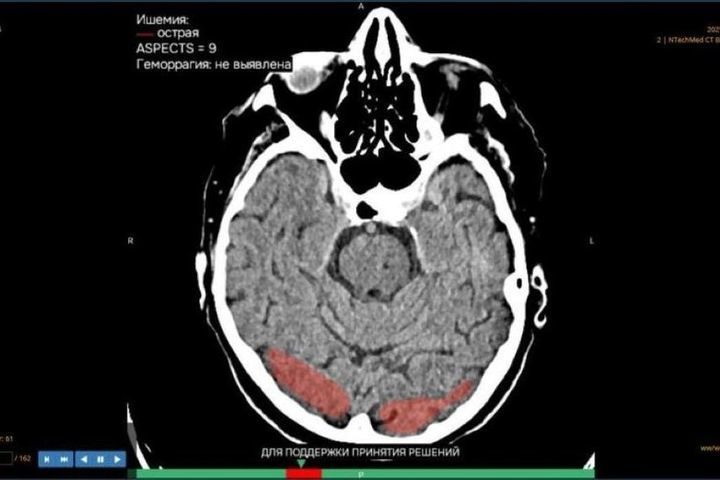

Благодаря работе с платформой «МосМедИИ» в Башкирии всего за два месяца искусственный интеллект помог изучить и проанализировать 1,7 тысячи медицинских изображений.

Башкортостан подключился к платформе одним из первых. Система объединяет 17 сервисов для анализа рентген-снимков, маммографии, КТ и флюорографии. На обработку 100 снимков платформе необходимо всего три минуты, а врачу - почти час.

Минздрав республики сообщает, что первыми к системе с искусственным интеллектом подключились горбольница №21 и Языковская центральная районная больница. Платформа является лишь вспомогательным инструментом для специалистов - окончательное заключение всегда выносит врач.